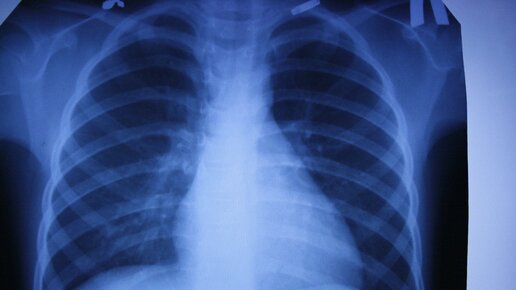

Можно ли по рентгену определить коронавирус?

Коронавирусная инфекция становится причиной поражения легочной ткани, поэтому большинство пациентов проходят рентгенологическое обследование.